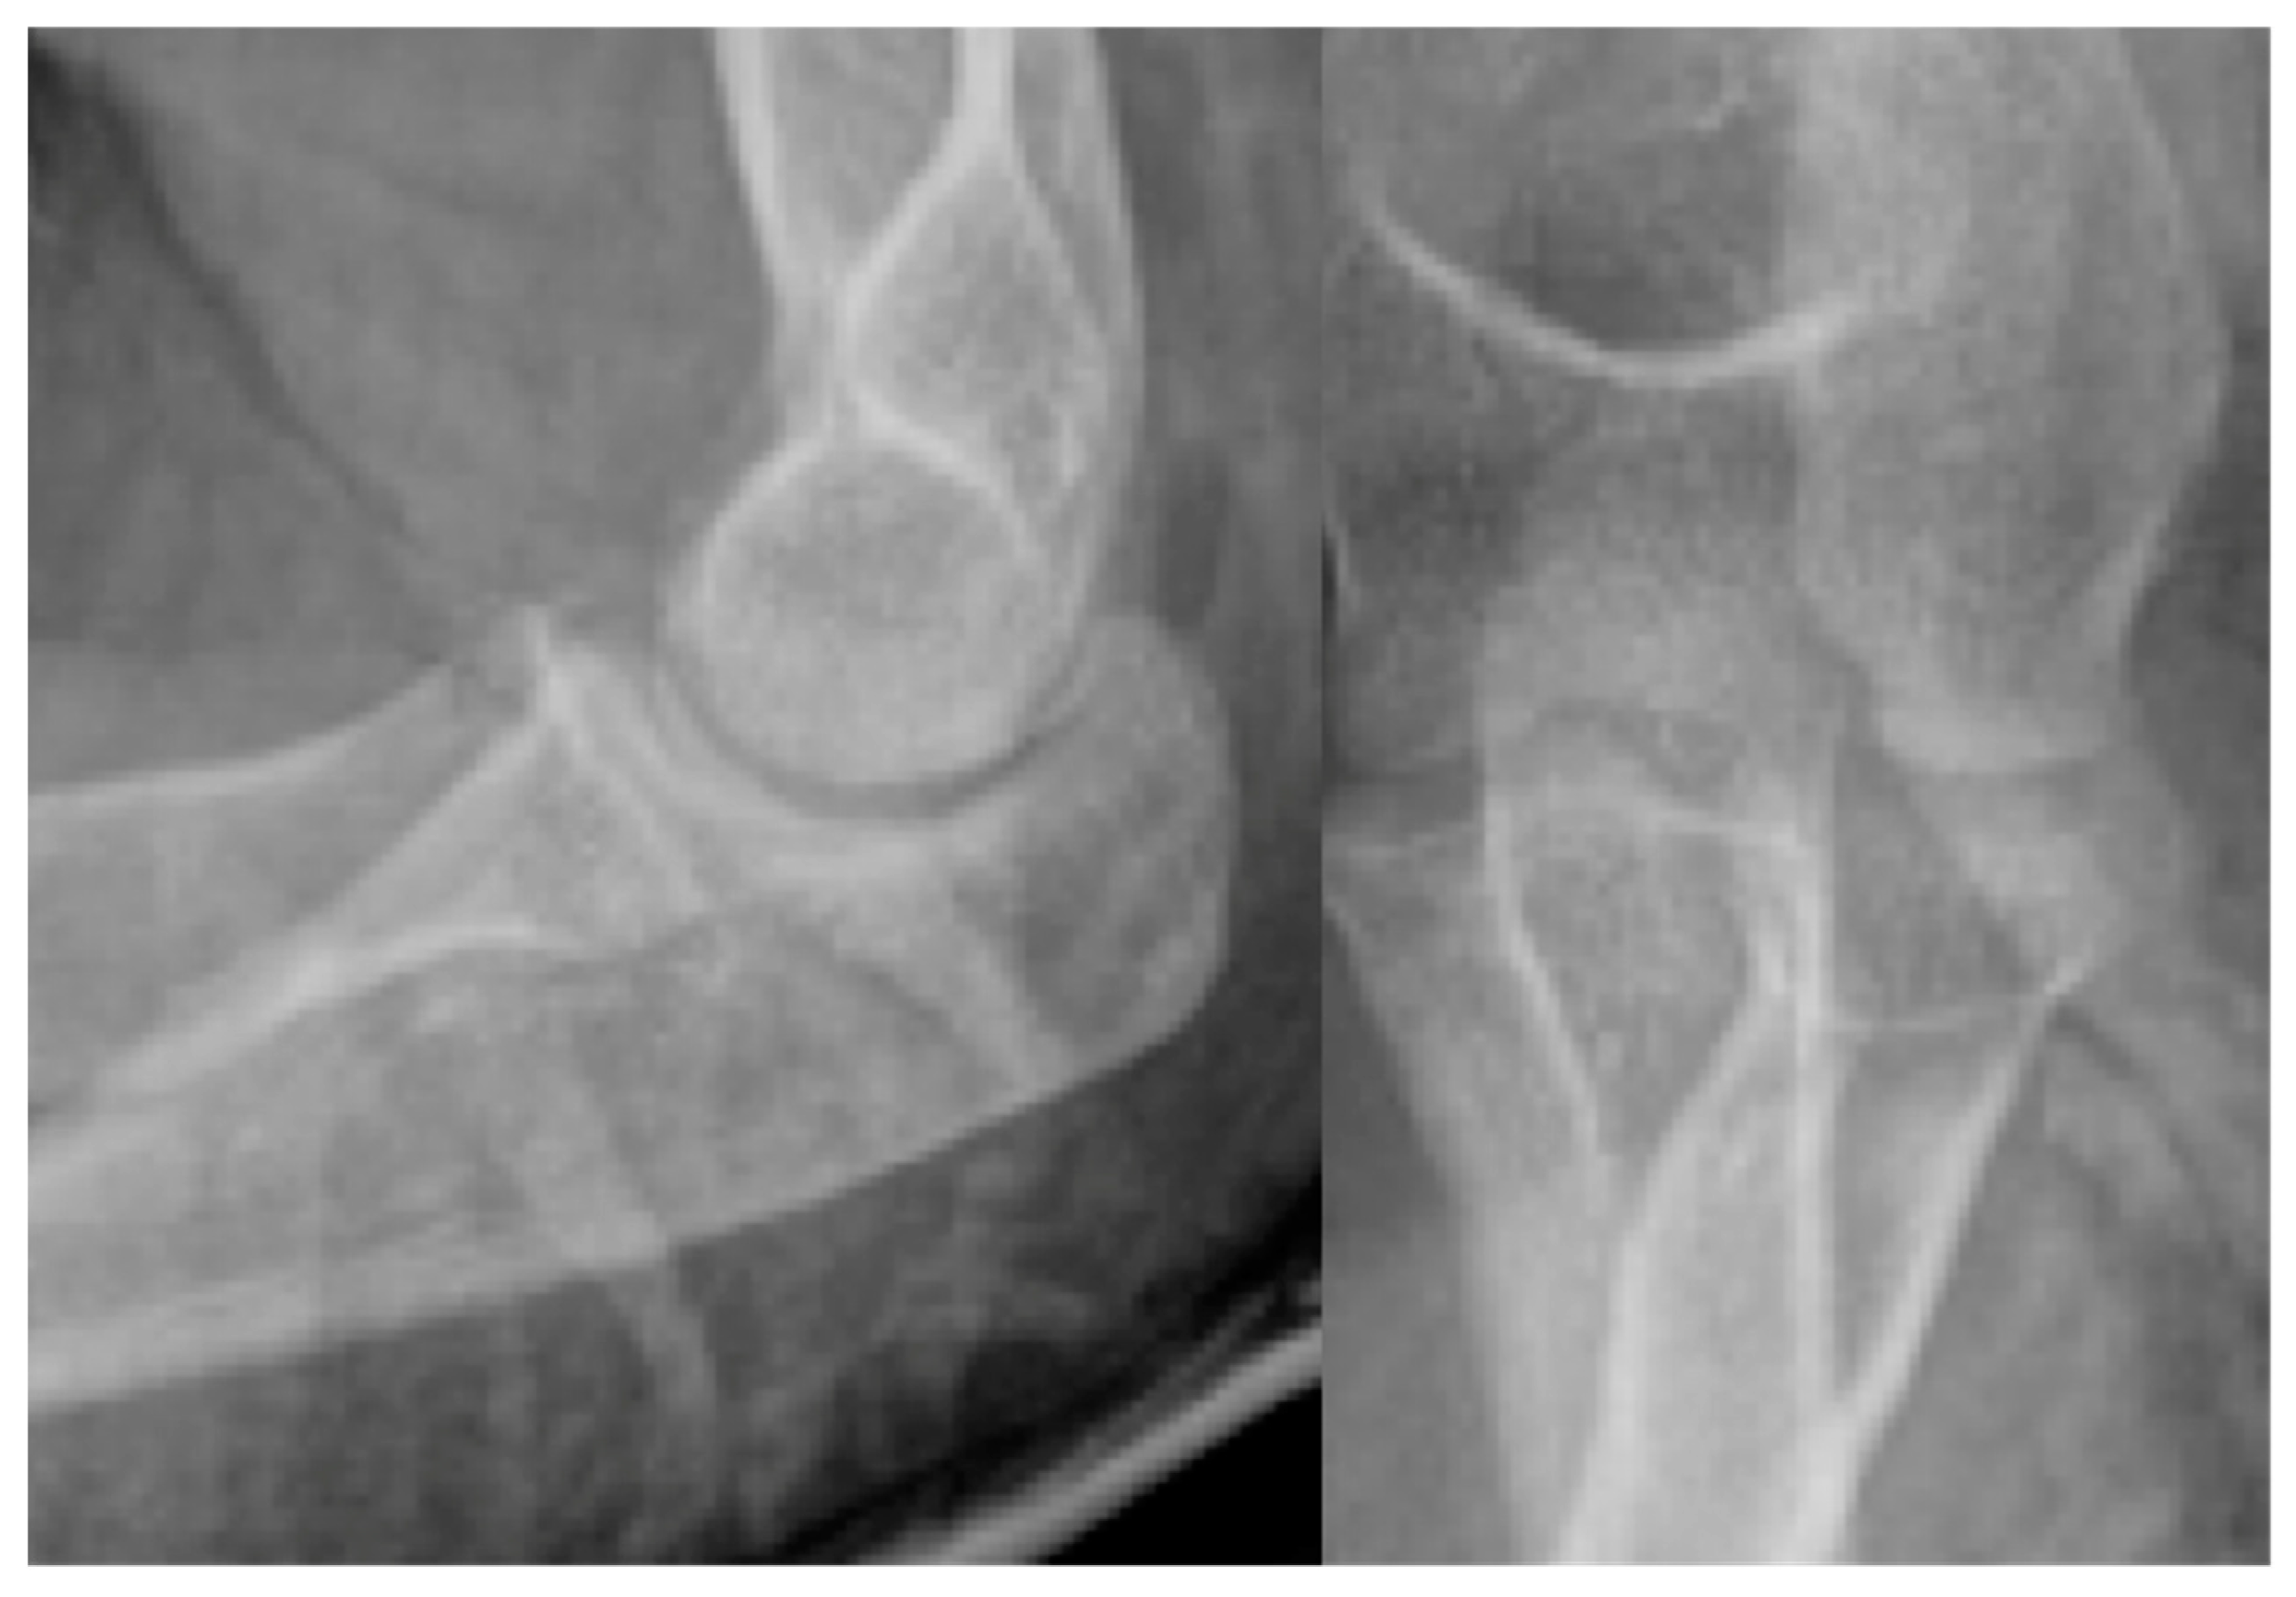

Stage IV:

- Osteochondral fragment is displaced

- Joint effusion

- X-ray: Loose body, lucency